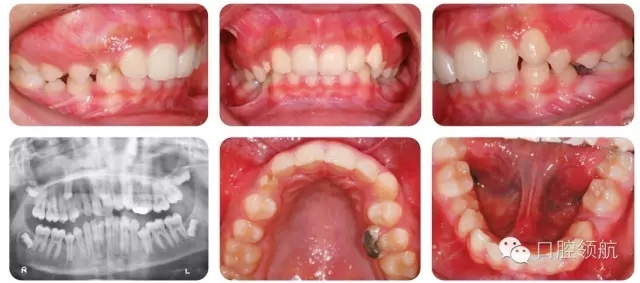

13歲的男性患者的錯牙合畸形如圖2.42所示。

全景片情況

● 全景片確認了該患者4顆第三磨牙均存在。

● UR3未萌出,牙冠略向遠中傾斜,并接近UR4的牙根。

● UR3根尖孔未閉合。

● 下頜雙側(cè)第二前磨牙垂直阻生。

● 未萌牙的發(fā)育無病理因素存在。

圖2.43顯示的是該患者的頭側(cè)位片,請總結(jié)其錯牙合情況

● 13歲男性患者,I類關系,輕度骨性II類,均面型。

● 雙側(cè)磨牙I類關系,中線齊,雙側(cè)尖牙1/2牙尖II類關系。

● 另外伴有:

○ 1. 異位UR3。

○ 下頜第二前磨牙阻生。

○ 深覆牙合。

○ 上下牙列均存在擁擠。